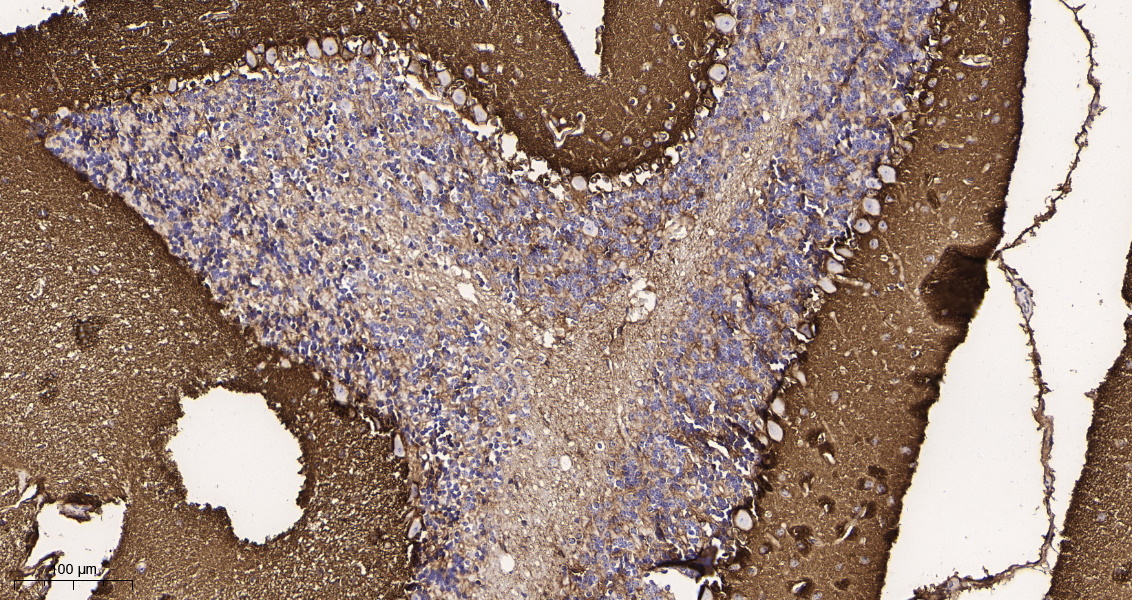

产品名称EAAT1 (5T15) Rabbit Monoclonal Antibody

推荐应用WB,IHC-P,IF-P,IF-F,IF-ICC,ELISA

稀释度IHC-P 1:200-1000, WB 1:500-2000, IF-P/IF-F/IF-ICC 1:200-1000, ELISA 1:5000-20000

背景介绍This gene encodes a member of a member of a high affinity glutamate transporter family. This gene functions in the termination of excitatory neurotransmission in central nervous system. Mutations are associated with episodic ataxia, Type 6. Alternative splicing results in multiple transcript variants.[provided by RefSeq, Feb 2014]

功能disease:Defects in SLC1A3 are the cause of episodic ataxia type 6 (EA6) [MIM:612656]. EA6 is characterized by episodic ataxia, seizures, migraine and alternating hemiplegia.,function:Transports L-glutamate and also L- and D-aspartate. Essential for terminating the postsynaptic action of glutamate by rapidly removing released glutamate from the synaptic cleft. Acts as a symport by cotransporting sodium.,PTM:Glycosylated.,similarity:Belongs to the sodium:dicarboxylate (SDF) symporter (TC 2.A.23) family.,tissue specificity:Highly expressed in cerebellum, but also found in frontal cortex, hippocampus and basal ganglia.